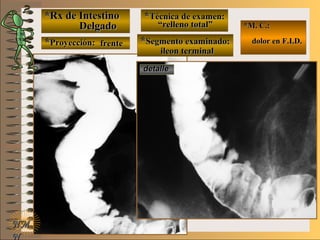

C-C-

**Segmento examinado:Segmento examinado:

*M. C.:*M. C.:

sin clínicasin clínica

NMNM

BBAA CC

E ME M

UNTUNT frentefrente

““relleno total”relleno total”

““mucosografía”mucosografía”

““doble contraste”doble contraste”

panorámicapanorámica

A-A-El examen es normal o patológico?El examen es normal o patológico?

Examen normal de estómago panorámico conExamen normal de estómago panorámico con

técnicas de : A- relleno total, B- mucosografíatécnicas de : A- relleno total, B- mucosografía

(tiene por objetivo reconocer el relieve interno(tiene por objetivo reconocer el relieve interno

grueso = a pliegues) y C- doble contraste (relievegrueso = a pliegues) y C- doble contraste (relieve

interno fino) en proyección de frenteinterno fino) en proyección de frente

B-B-Puede describir la o las imágenesPuede describir la o las imágenes

**OpciónOpción

de volverde volver